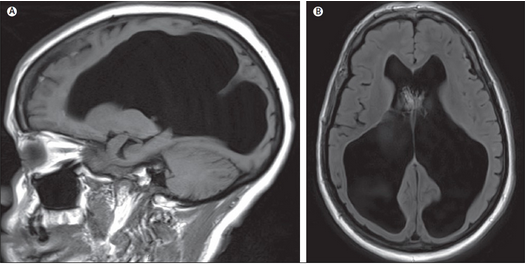

Гидроцефалия у младенца

Гидроцефалия у младенца 116 фотографий